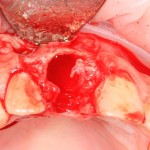

Немедленная имплантация — оптимальное решение в любой клинической ситуации